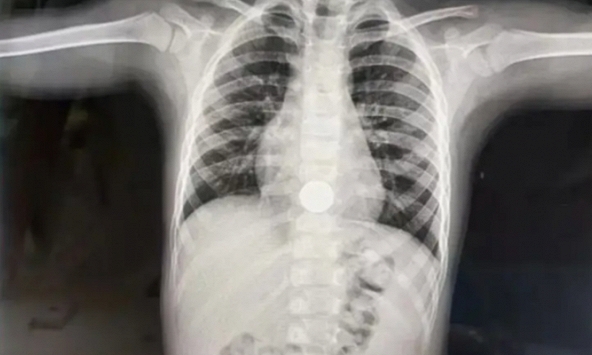

Tuy nhiên sau đó, cậu bé bắt đầu xuất hiện những biểu hiện bất thường như chán ăn, ngứa ngáy và khó chịu ở lòng bàn tay, bàn chân cũng như không thể đi đại tiện trong vài ngày, bắt đầu có những cơn sốt.

Khi thấy những dấu hiệu bất thường của con, mẹ của Wa Wa đã vội bế con tới bệnh viện. Sau khi kiểm tra, bác sĩ cho biết nguyên nhân là bởi ăn quá nhiều sầu riêng. Cô Trương - mẹ Wa Wa cũng cho hay, bản thân trong thời gian này cũng ăn khá nhiều nên có nổi mụn và tăng cân.